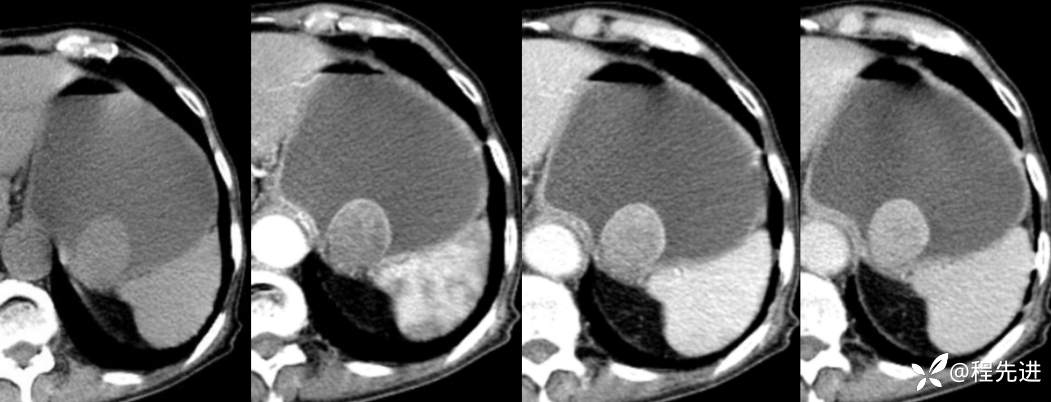

局部放大